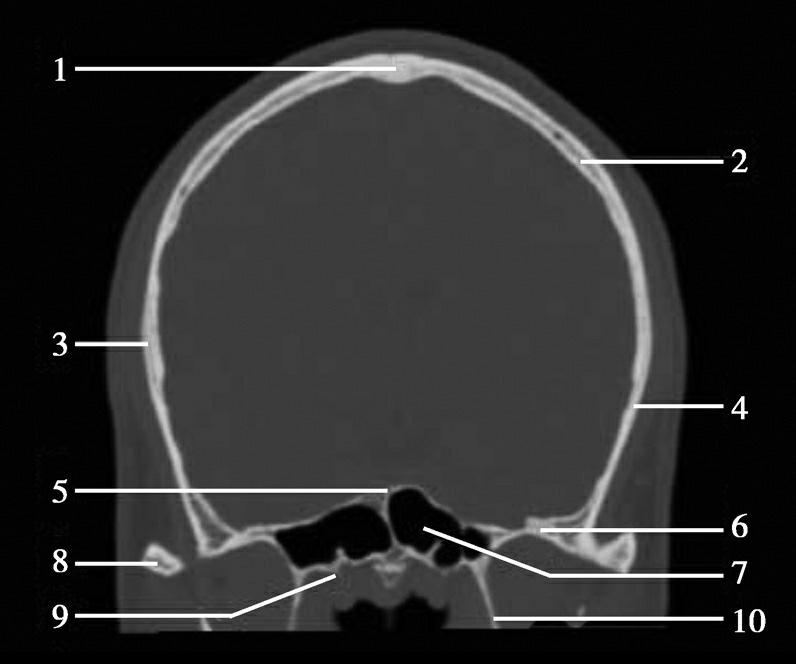

图1-2-2 颅底层面(骨窗)

A.横断面;B.横断面标注

1.鼻骨;2.筛窦纸板;3.颧骨眶突;4.翼腭窝;5.蝶骨大翼;6.卵圆孔;7.破裂孔;8.颞骨颧突;9.棘孔;10.斜坡;11.颞骨岩部;12.乳突;13.颈静脉孔;14.枕乳突缝;15.枕骨;16.枕内隆凸

层面前部呈开口向前的“V”字形,正中为鼻中隔,向两侧依次为筛窦和眼眶,眼眶内前部为眼球,后部为眶脂体。翼腭窝位于眼眶后部,窝内含有脂肪并有上颌神经通过。层面中部为蝶骨体,蝶骨体中部可见含气蝶窦,蝶窦后方为枕骨基底部,两者呈前后关系,其上面构成斜坡。蝶窦两侧为蝶骨大翼,其后外侧缘处由前向后可见卵圆孔和棘孔,分别有下颌神经和脑膜中动脉通过。斜坡外侧、岩骨尖前方为破裂孔。蝶骨大翼与眶外侧壁的颧骨借颧弓相连,颧弓和蝶骨大翼之间有咬肌及颞肌。层面中部外侧为外耳道。颞骨岩部呈“八”字形,相互之间借破裂孔软骨、蝶岩软骨结合和岩枕软骨结合连接。岩部后外侧的乳突部内可见乳突小房,乳突部与枕骨相接。岩骨后部可见颈静脉孔,内有颈内静脉、舌咽神经、迷走神经和副神经通过。层面后部为颅后窝,其内可见延髓,延髓前方为延髓前池,内有椎动脉,后外侧为小脑半球下部,后方为第四脑室、小脑扁桃体及小脑蚓部。

破裂孔、卵圆孔、棘孔及斜坡等均为重要的解剖结构,临床常见疾病如鼻咽癌常侵犯上述结构(图1-2-3)。颈静脉孔区较常见的肿瘤为颈静脉球瘤,常伴有颈静脉孔及其邻近骨质的破坏(图1-2-4)。